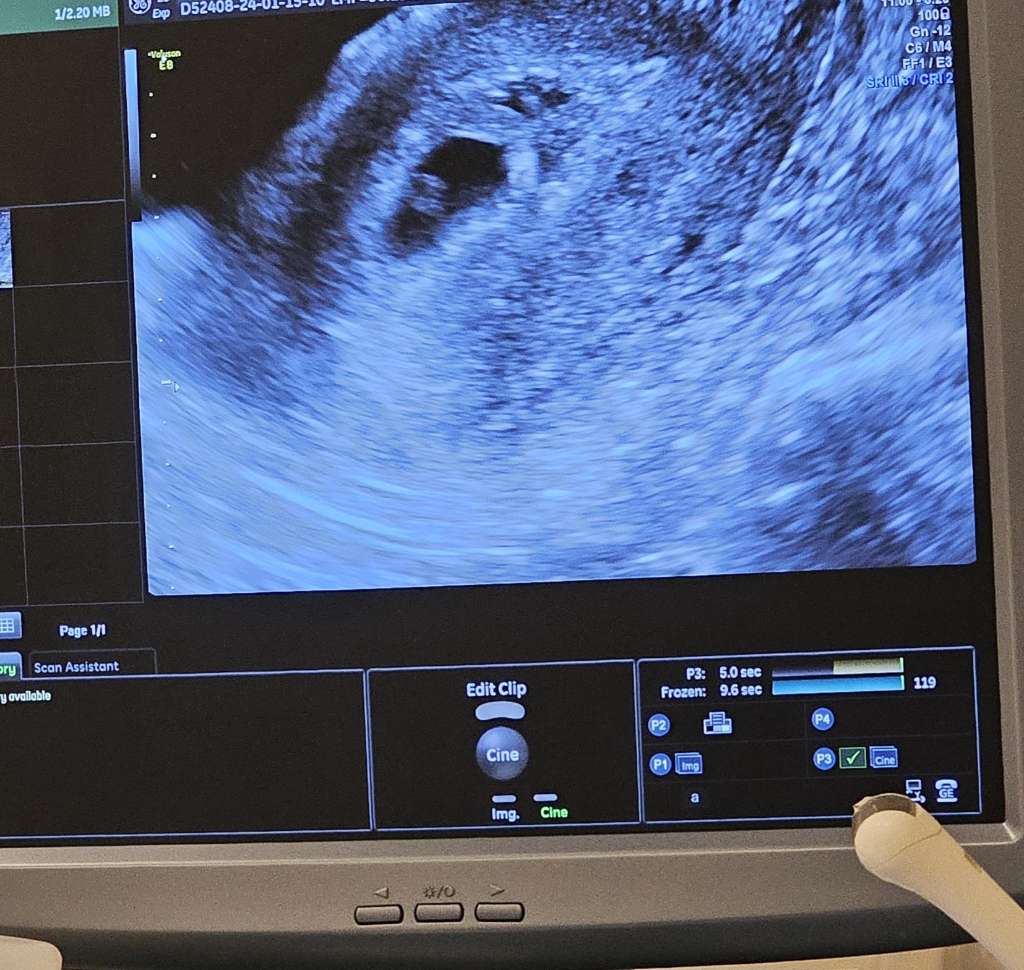

Ja dziś 6+4 czyli wg ginekologicznego 7my tydzień.

No i najważniejsze - w jamie macicy 3mm zarodek z bijącym serduszkiem 🥰

Tak, pulsujący punkcik i to taki jak główka szpilki 🥺 Takie maleńkie. Pierwszy raz widziałam bo na NFZ tylko powiedzial, że jest ciąża bez człowieka i nawet nie pokazał ekranu 🙄 A tu nawet sobie zdjęcie na sprzęcie machnęłam 😂